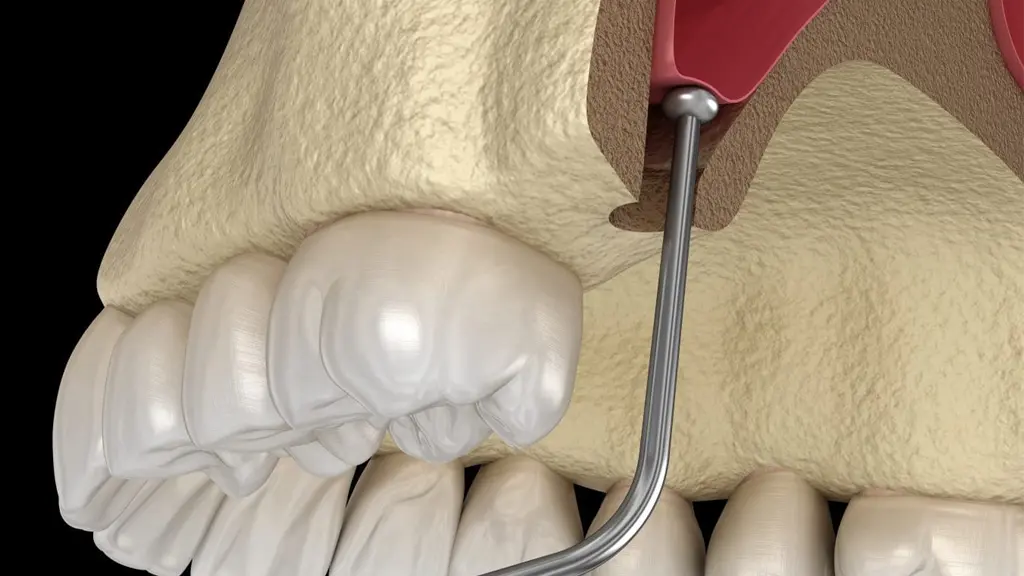

- بدون برش لثه (در برخی موارد): با استفاده از راهنمای جراحی دیجیتال، بسیاری از مراحل بدون نیاز به جراحی باز انجام میشوند.

- کاشت ایمپلنت با حداقل تهاجم

به دلیل استفاده از راهنمای جراحی دیجیتال، مراحل کاشت بسیار سریعتر و کمتهاجمیتر انجام میگیرند. - بدون نیاز به بخیه در بسیاری از موارد

در این روش، برش لثه به حداقل رسیده یا کاملاً حذف میشود که باعث کاهش درد، خونریزی و تورم میگردد. - زیبایی طبیعی و هماهنگ با لبخند شما

- ساخت گاید جراحی (راهنمای دقیق برای کاشت)

- کاشت ایمپلنت با دقت میلیمتری و حداقل تهاجم